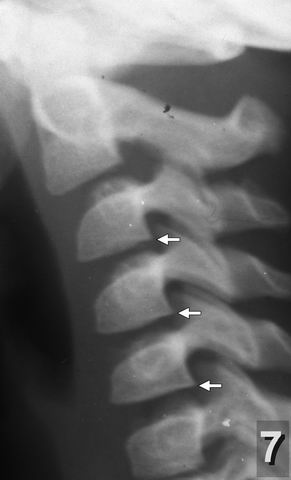

Хочу обратить внимание на следующее немаловажное обстоятельство. У детей с клиническими проявлениями последствий родовых травм шейного отдела уже с дошкольного возраста при рентгенографии наряду с симптомами перенесённых повреждений позвоночника нередко обнаруживался так называемый "спондилёз" - разрастание костных шипов (остеофитов) по краям тел позвонков (рентгенограмма 7) - признак хронического дегенеративно-дистрофического заболевания позвоночника, диагностируемого чаще всего после 40-50 лет. У взрослых при локализации процесса в шейном отделе характерными его проявлениями являются стойкий болевой синдром в шее, плечевом поясе, а также выраженные сосудистые нарушения головного мозга. В моих наблюдениях костные шипы на рентгенограммах у детей чаще всего обнаруживались в области I и II шейных позвонков (рентгенограмма 8 ) и являлись причиной упорных головных болей, острых нарушений мозгового кровообращения, "хруста" и болей в шее и другой патологии.

o" width="95" height="158" alt="Рентгенограмма 7" align="left" />Рентгенограмма 7 реб. Д. 6 лет Симптом "струны". Остеофиты на наружно-задней поверхности тел III - V шейных позвонков.